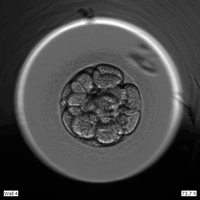

In the traditional IVF process, after oocyte retrieval, embryos are cultured in the lab for five days before the doctor selects the best one for transfer. During this time, patients have no insight into their embryo’s development—they can only wait for the final result, in anxious and helpless.

"These five days are like opening a blind box," said professor Sun. "That’s why we pioneered the integration of time-lapse embryo imaging with blockchain technology, developing the MyBaby Smart Reproductive Medicine Project—allowing patients to track their embryo’s growth in real-time and see every change happening in the lab."

On one hand, MyBaby achieves full visualization and traceability of embryo development, making lab quality control transparent. This creates a value-driven, emotionally supportive platform, helping patients with implantation issues build an early emotional bond with their embryo and boosting their confidence in treatment success.

On the other hand, by combining time-lapse imaging, embryo development parameters, and lab environmental data, the system establishes a new embryo evaluation standard, laying the foundation for AI-powered embryo grading and improving treatment quality for implantation disorders.

"In the past, patients often misunderstood the process due to lack of transparency—some even worried the lab might 'lose' their embryo," professor Sun said. Now, with MyBaby, parents can witness their baby’s journey from a single cell, while doctors’ procedures become more precise and transparent.